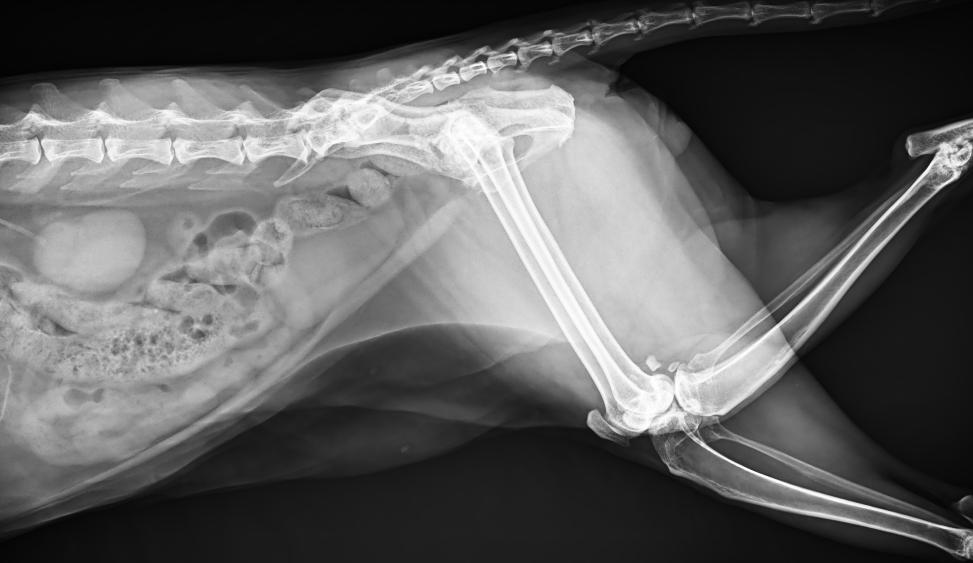

● 進口高品質(zhì)球管,大功率、高熱容量、微焦點,1.0/2.0mm雙焦點設(shè)計

● 25kHz高主逆變頻率,輸出電壓更穩(wěn)定;瞬時定格影像,無拖尾現(xiàn)象

● 可浮動床面設(shè)計,滿足大部分中小型寵物檢查

● 靈巧機架設(shè)計,近臺操作,手動/遙控曝光,結(jié)構(gòu)靈活緊湊